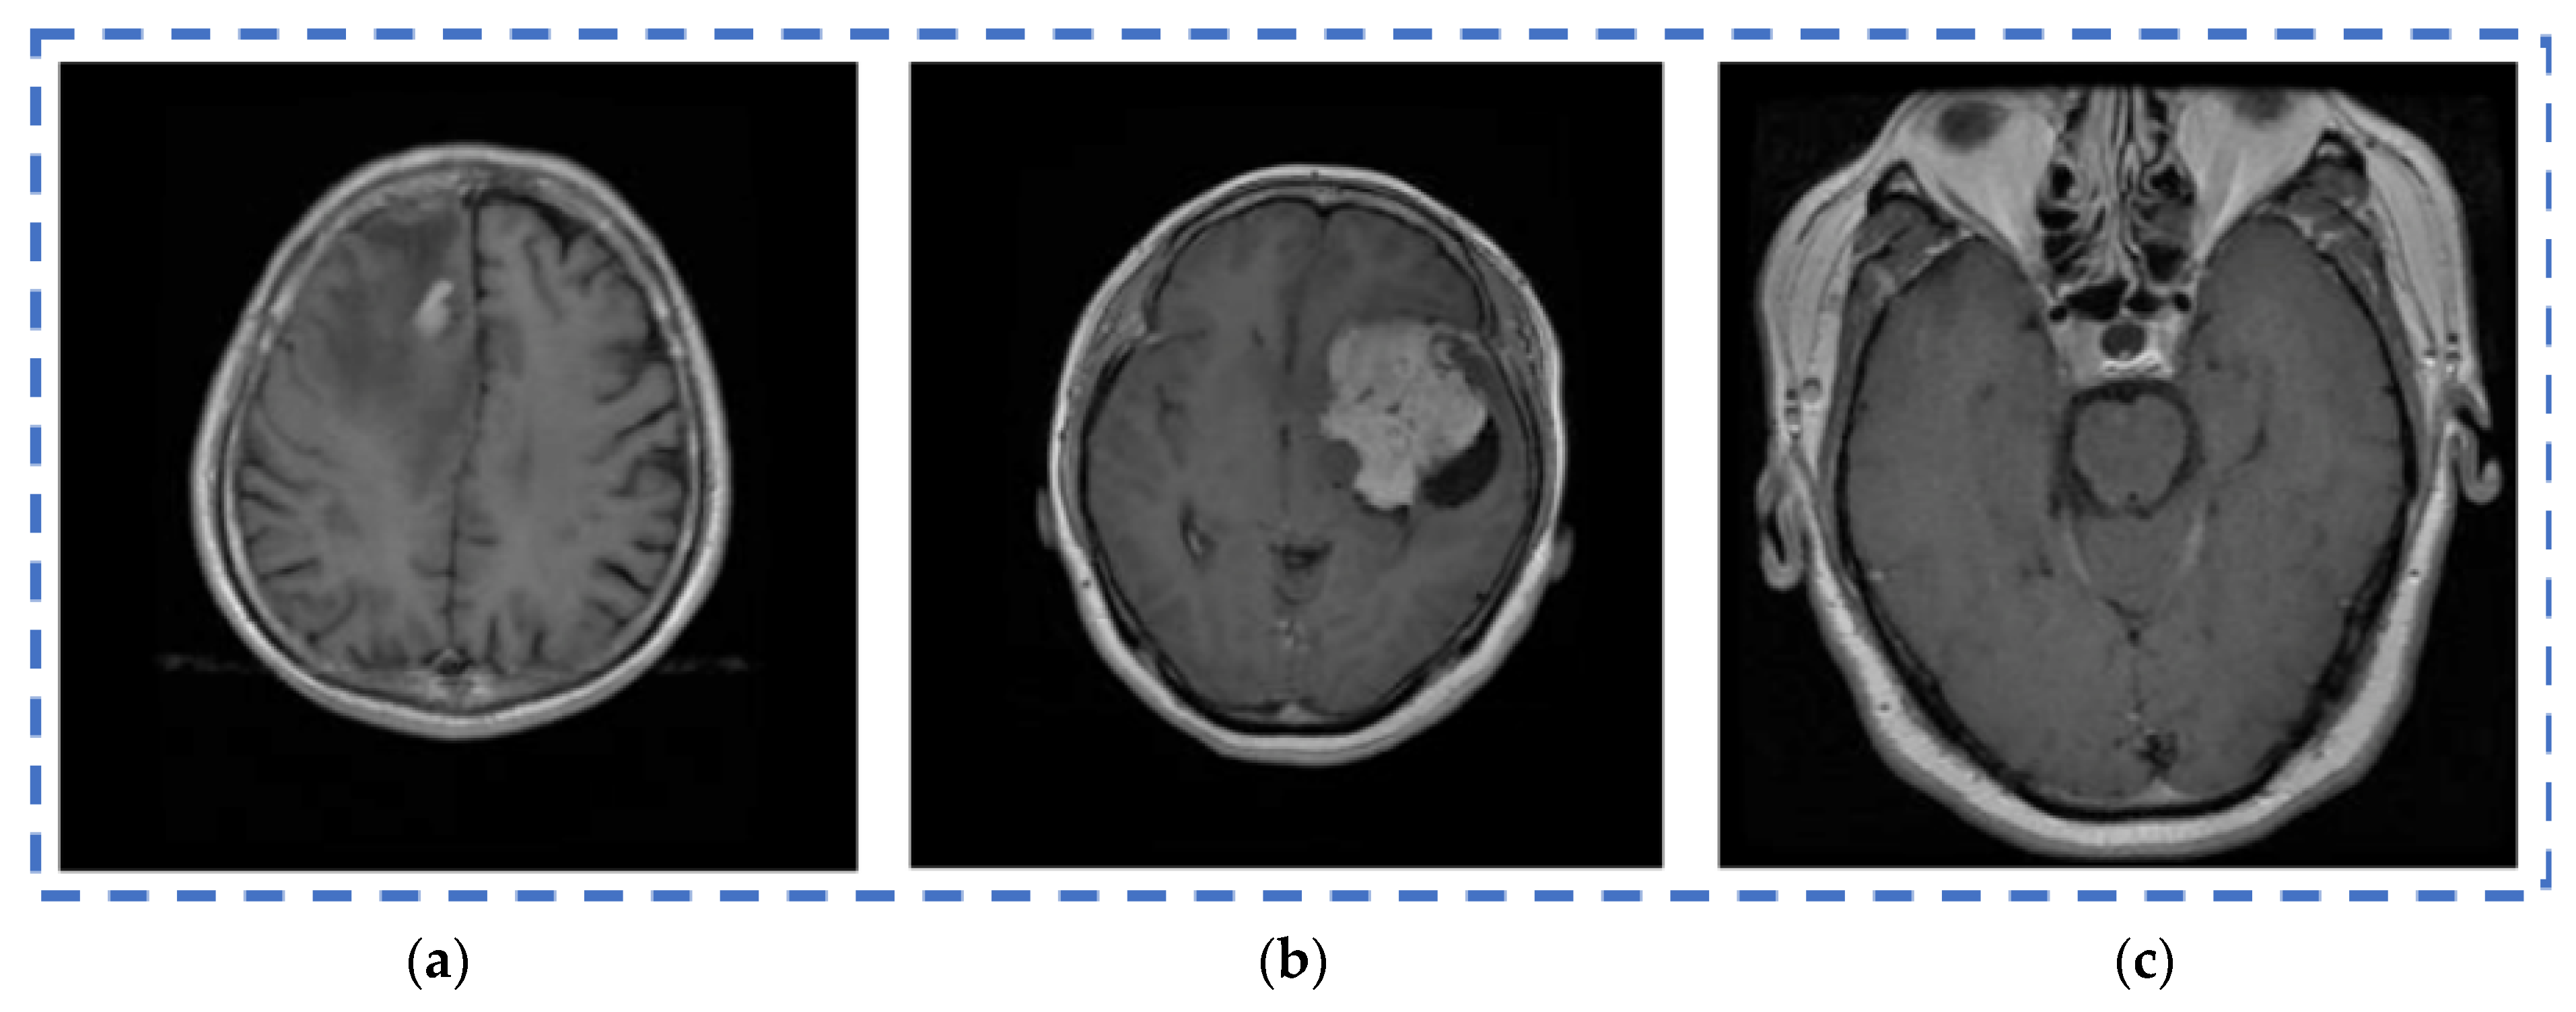

| Input (Image) | Segmented Image | Tumor Type | Tumor-Affected Portion | Total Count of Defective Cells |

|---|---|---|---|---|

|  |  | Glioma | 28.521 | 18,112 |

|  | Not required for benign images. | Benign | 0 | 0 |

|  |  | Meningioma | 19.131 | 4951 |

|  |  | Pituitary | 23.1910 | 5361 |